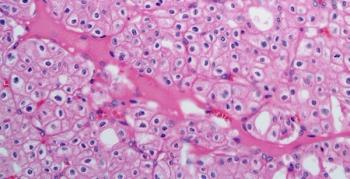

A 20-year-old young man presents with hypertension and a left kidney mass. After further evaluation, a biopsy is performed. What is your diagnosis?

A 47-year-old man presents with pain in the right flank. A kidney mass is found on imaging.

A 63-year-old man presents with a mass in the left kidney. After further evaluation, a biopsy is performed. What is your diagnosis?